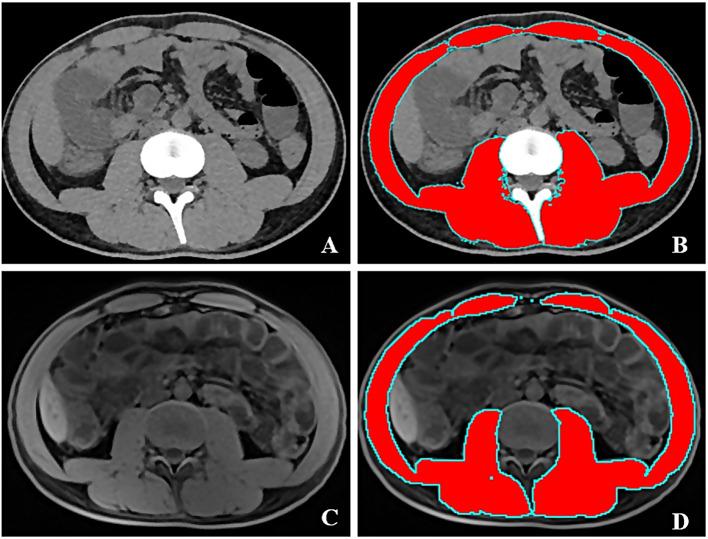

Sarcopenia and anemia are common complications in patients with Crohn's Disease (CD). However, few studies have shown the association between sarcopenia and hemoglobin levels in CD patients. This retrospective study aimed to explore such association in Chinese patients with CD. Two hundred and twelve adult CD inpatients who underwent computed tomography (CT) or magnetic resonance imaging (MRI) examinations from July 2019 to December 2021 were included in the study. Sarcopenia was defined according to the cutoff value of skeletal muscle index of lumbar spine 3 (SMI-L3) (< 44.77cm/m for males and < 32.5cm/m for females). The CD patients were divided into two groups based on the presence or absence of sarcopenia. Clinical data, hemoglobin levels, and other laboratory data were retrospectively collected. The association between hemoglobin levels and sarcopenia was analyzed by univariable and multivariable logistic regression analysis. Sarcopenia occurred in 114 CD patients (53.8%). Compared to patients without sarcopenia, patients with sarcopenia had a lower proportion of L1 (30.7% vs. 45.8%, p = 0.032) and B1 classification (58.8% vs. 72.4%, p = 0.037). Patients with sarcopenia had significantly lower levels of hemoglobin (Hb) (116.5 ± 22.8 vs. 128.1 ± 21.0, p < 0.001). The prevalence of sarcopenia increased with the decrease in hemoglobin level (p for trend < 0.05). Linear regression analysis showed that hemoglobin levels were associated with SMI-L3 (β = 0.091, p = 0.001). Multivariable logistic regression analysis found that higher hemoglobin levels (OR:0.944; 95% CI: 0.947,0.998; p = 0.036) were independent protective factors for sarcopenia. Lower hemoglobin levels are independently associated factors of sarcopenia in adult Chinese patients with CD.